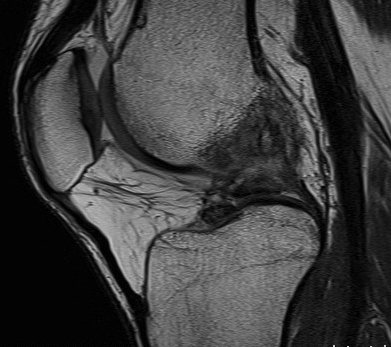

T1 weighted films

- fat has a bright signal e.g. bone marrow

- those tissues with little fat or water e.g. cortical bone, tendons, ligaments are dark in both T1 & T2

Standard workhorse for anatomy